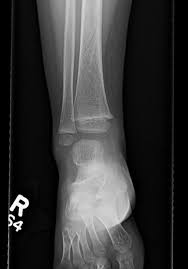

Two spiral fractures sustained following only minor trauma. Complete fractures are categorized based on the way the bone breaks. It occurs due to a rotational, or twisting, force. Try our newest study sets that focus on spiral fracture to increase your studying efficiency and retention. Detailed step by step desription of intramedullary nailing for simple fracture, spiral located in our module intramedullary fixation is valuable and appropriate for the majority of tibial fractures. Other articles where spiral fracture is discussed: A spiral fracture is a bone fracture occurring when torque is applied along the axis of a bone.1 spiral fractures often occur when the body is in motion while one extremity is planted. Spiral fracture femur (there is a significantly displaced spiral fracture of the proximal femoral. A spiral fracture, also known as torsion fracture, is a type of complete fracture. A spiral fracture is a bone fracture caused by a twisting force. A spiral fracture is usually treated right away with surgery. Summary summary (text) medline pmcid list. Know ways to lower your risks in the first place.

A fracture, sometimes called a torsion fracture, in which a bone has been twisted apart. Shiel jr., md, facp, facr. A spiral fracture is a bone fracture occurring when torque is applied along the axis of a bone. Other articles where spiral fracture is discussed: Summary summary (text) medline pmcid list. It occurs due to a rotational, or twisting, force. Detailed step by step desription of intramedullary nailing for simple fracture, spiral located in our module intramedullary fixation is valuable and appropriate for the majority of tibial fractures. Also called a torsion fracture, a spiral my son suffered a spiral femur fracture and the er doctor didn't report it.

Spiral fracture femur (there is a significantly displaced spiral fracture of the proximal femoral. A spiral fracture is usually treated right away with surgery. Summary summary (text) medline pmcid list. A spiral fracture is a bone fracture that occurs when a long bone is broken by a twisting force. Also called a torsion fracture, a spiral my son suffered a spiral femur fracture and the er doctor didn't report it. It occurs due to a rotational, or twisting, force. Detailed step by step desription of intramedullary nailing for simple fracture, spiral located in our module intramedullary fixation is valuable and appropriate for the majority of tibial fractures. Medical definition of spiral fracture. Spiral fractures are complete fractures of long bones that result from a rotational force applied to the figure 1. Spiral fractures are usually the result of high energy trauma and are likely to be associated with. Try our newest study sets that focus on spiral fracture to increase your studying efficiency and retention. Bone depressed fracture fractures simple fracture closed reduction. Finally, two days later, the other.